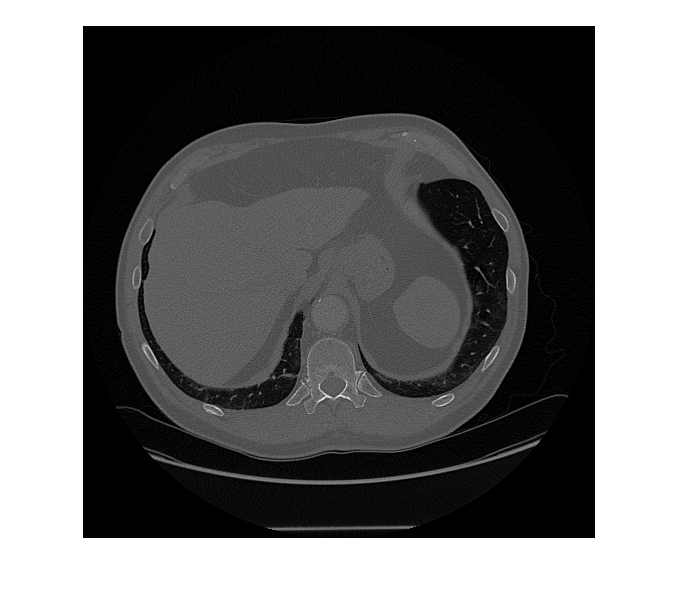

segments objects from an image of size mask,score] = segmentObjectsFromEmbeddings(medsam,embeddings,imageSize,BoundingBox=boxPrompt)imageSize using the Medical

Segment Anything Model (MedSAM) image embeddings embeddings and the

bounding box coordinates boxPrompt as a visual prompt, and returns the

predicted object mask mask and the corresponding prediction score

score.